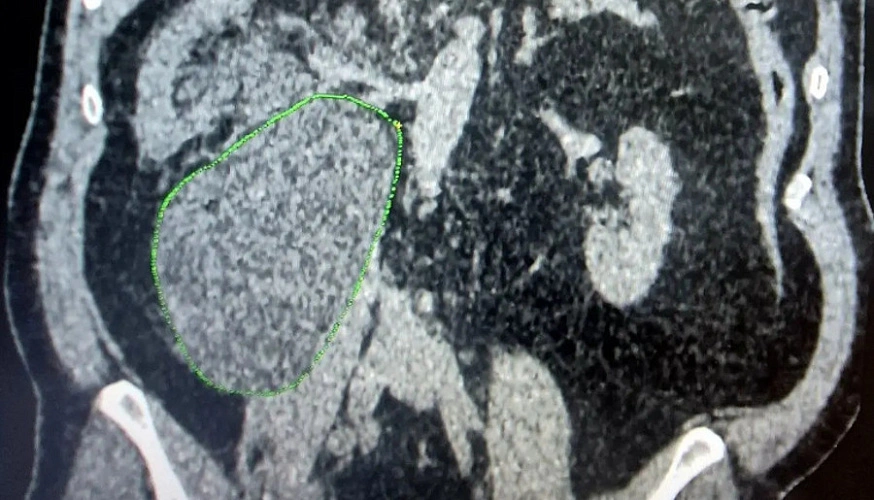

У одного из жителей города Балаково в забрюшинном пространстве образовалось массивное скопление жидкости - уриному. Это крайне редкая и опасная патология, и балаковским врачам удалось спасти пациента.

Как сообщает Балаковская городская клиническая больница (БГКБ), уриному в забрюшном пространстве обнаружили у 62-летнего. Месяц назад мужчине провели плановую операцию по удалению кисты почки в одной из ведущих клиник Саратова. Через две недели после выписки дома начались сильные боли в правой половине живота. Обезболивающие не помогали, живот стал асимметричным, а каждое движение доставляло мучение, и после постановки диагноза балаковским врачам пришлось экстренно вмешиваться.

Уринома (скопление мочи вне мочевыводящих путей) опасна тем, что может привести к интоксикации организма, потери почки и перитониту, смертельно опасному воспалению. Это крайне редкое осложнение, и оно встречается всего в 3-5% случаев. Это индивидуальная, непредсказуемая реакция организма на сложное хирургическое вмешательство, возникающая действительно редко.

«Ситуация была критической: объем скопившейся мочи составил 1,5 литра. Это огромное образование не только вызывало невыносимую боль, но и сдавливало почку, мешая её нормальной работе. Действовать нужно было быстро. Для обеспечения максимальной точности манипуляций врачи-урологи обратились за помощью к коллегам из отделения травматологии - взяли передвижной аппарат УЗИ. Под непрерывным ультразвуковым контролем, врач Моршед Махфуз Ахмед Абдаух провел пункцию и установил дренажную трубку», - рассказали в БГКБ.

Медики рассказали, что результат последовал незамедлительно: уже через два часа после эвакуации жидкости пациент смог самостоятельно ходить, а боль отступила. Чтобы отверстие затянулось без повторной открытой операции, пациенту установят внутренний стент. Это позволит обеспечить полную герметичность системы и даст тканям возможность восстановиться самостоятельно.